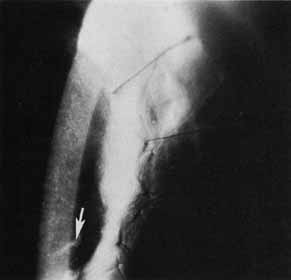

The current number of procedures performed on an annual basis is decreasing slightly; a total of 32,744 corneal transplants were performed in 2002, marking the first time since 1986 that the number of procedures performed has been less than 33,000.1 This downward trend has coincided with the decrease in incidence of pseudophakic corneal edema (PCE) (Fig. 1) and aphakic corneal edema (ACE). The percentage of PKs performed to treat PCE has dropped from 19.8% in 2001 to 18.4% in 2002, which was the lowest percent reported in this category in 15 total years of tracking by the Eye Bank Association of America (EBAA). It is possible that this decrease reflects improved cataract removal technique and technology, such as phacoemulsification and posterior chamber intraocular lens placement. The indications for PK have shifted over the past several decades, with PCE the most common indication since 1980, whereas keratoconus (Fig. 2) and ACE were the most common indications prior to 1980.2 Data is tracked for a total of 16 indications for transplant by the EBAA. Pseudophakic corneal edema, keratoconus (particularly in younger patients), Fuchs' endothelial dystrophy (particularly in older patients), and regrafting secondary to rejection or other reasons currently sit atop the list of indications for PK.

Fig. 2 Keratoconus is one of the most common indications for penetrating keratoplasty. Descemet's tears may occur spontaneously in this condition, leading to acute hydrops.